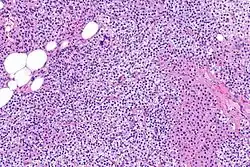

Hyperparathyroidism, in general, is caused by either tumorous growth in one or more parathyroid glands or a prolonged decrease in blood calcium levels or hypocalcaemia which in turn stimulates the production of parathyroid hormone release from the parathyroid gland.[10][11] The parathyroid gland is located beside the thyroid gland in the neck, below and in front of the larynx and above the trachea. It is composed of four glands in total that monitor blood calcium levels via the calcium sensing receptors, a g-coupled protein receptor.[12] The parathyroid glands main role is calcium homeostasis.[13][12] Histologically, these glands are composed of chief cells and oxyphil cells with the chief cell primarily responsible for the storing and release of parathyroid hormone. These cells are arranged in a pseudo-follicular pattern similar to the thyroid follicles. Keratin staining is used to image the parathyroid hormone granules.[9][14]

Primary hyperplasia of the parathyroid gland, results from both hypocalcaemia and increased phosphate levels by decreasing expression of calcium sensing receptors and vitamin D receptors at the parathyroid gland.[8][4] These decreases in receptor expression lead to hyperfunctioning of the parathyroid. Hyperfunction of the parathyroid gland is thought to exacerbate primary hyperplasia which evolves further to a secondary more aggressive hyperplasia. Histologically, these hyperplasic glands can be either diffuse or nodular.[24] Primary hyperplasia, usually resulting in diffuse polyclonal growth is manly related to reversible secondary hyperparathyroidism. Secondary hyperplasia of the parathyroid gland is more often a nodular, monoclonal growth that sustains secondary hyperparathyroidism and is the catalyst in the progression to tertiary hyperparathyroidism. Nodular hyperplastic glands in tertiary hyperparathyroidism are distinctly larger in both absolute size and weight up to 20-40-fold increases have been reported.[25][26][24]

Parathyroid glands are normally composed of chief cells, adipocytes and scattered oxyphil cells.[27][14] Chief cells are thought to be responsible for the production, storage and secretion of parathyroid hormone. These cells appear light and dark with a prominent Golgi body and endoplasmic reticulum. In electron micrographs, secretory vesicles can be seen in and around the Golgi and at the cell membrane. These cells also contain prominent cytoplasmic adipose.[27][14] Upon onset of hyperplasia these cells are described as having a nodular pattern with enlargement of protein synthesis machinery such as the endoplasmic reticulum and Golgi. Increased secretory vesicles are seen and decreased intercellular fat is characteristic.[27][24] Oxyphil cells also appear hyperplasic however, these cells are much less prominent.